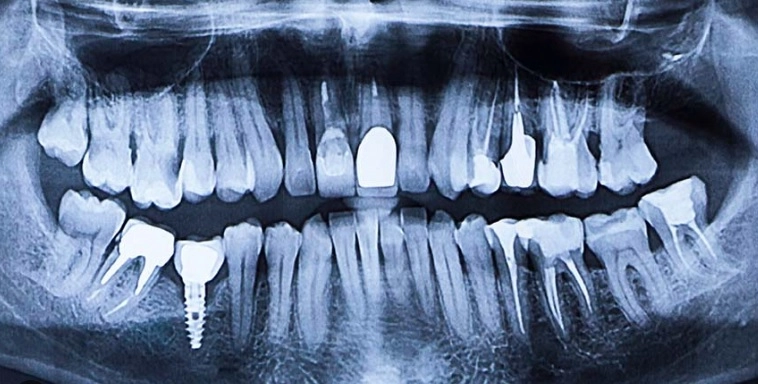

Ортопантомограмма (ОПТГ), или панорамный снимок зубов, — это один из самых востребованных и информативных методов рентгенодиагностики в современной стоматологии. По сути, это детальное двухмерное изображение всей зубочелюстной системы, на котором одновременно видны все зубы верхней и нижней челюсти, височно-нижнечелюстные суставы, гайморовы пазухи и другие структуры лицевого скелета. В отличие от прицельного снимка, который показывает только один-два зуба, ортопантомограмма даёт врачу целостную картину, позволяя увидеть взаимосвязи и скрытые патологические процессы.

Состояние зубов и пломб. На снимке видны все кариозные полости, в том числе скрытые и расположенные между зубами, качество пломбирования корневых каналов (насколько плотно и до верхушки они заполнены), наличие перфораций и отломков инструментов в каналах.

Положение зубов мудрости. ОПТГ незаменима для оценки ретенции и дистопии «восьмёрок». Врач видит направление их роста, форму и количество корней, их близость к нижнечелюстному каналу и гайморовым пазухам, что необходимо для планирования сложного удаления.

Состояние костной ткани. Снимок позволяет выявить начальные признаки пародонтита (убыль костной ткани), кисты, гранулёмы, одонтогенные опухоли и другие новообразования, которые могут долгое время развиваться бессимптомно.

Состояние височно-нижнечелюстных суставов. Хотя для детальной диагностики суставов чаще требуется КТ, ОПТГ даёт общее представление о симметричности суставных головок и ширине суставной щели.

Состояние гайморовых пазух. Врач может увидеть утолщение слизистой, наличие кист или полипов, а также попадание инородных тел (например, корней зубов) в пазуху.

Эффективность лечения. Контрольные снимки необходимы после эндодонтического лечения, перед протезированием и имплантацией, а также в процессе ортодонтической коррекции.